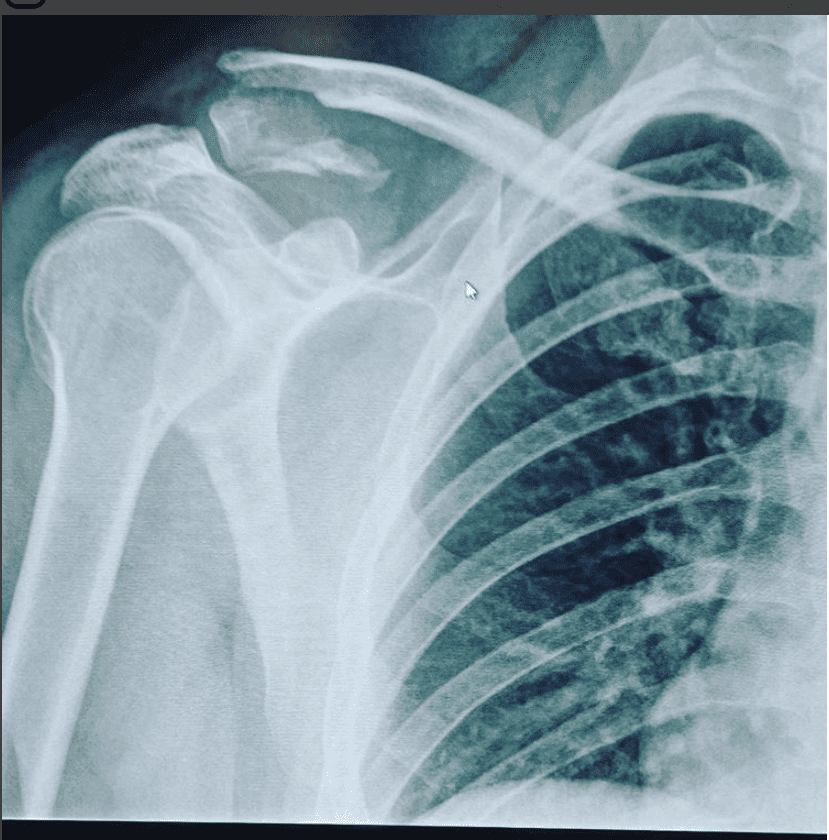

Drog min ac på endurot i Vallåsen i maj. Sjukvårdare på plats trodde att det endast var en blödning och läkaren som jag besökte en månad senare konstaterade också att det bara var en blödning. När jag röntgade axeln för 2 veckor sedan så var det en ac lux grad 3 plus att jag har haft en fraktur på nyckelbenet. Jag undrar ifall någon med erfarenhet av en sådan skada vet ifall jag är sent ute för att få ordning på axeln och hur känslig är axeln för ytterligare smällar?

Grad III är ett träsk.....Sök på pubmed så ser du. Läste in mig lite på ämnet för många år sedan som ett tänkt examensarbete. Verkar inte finnas någon konsensus än. För att göra en lång historia kort: man får göra bedömning från fall till fall. Hoppas du blir omhändertagen nu. Det där låter inte optimalt handlagt med en massa antaganden. Av bilden att döma skulle röntgen gjorts akut, man ser ju tydligt att du har en AC-lux.